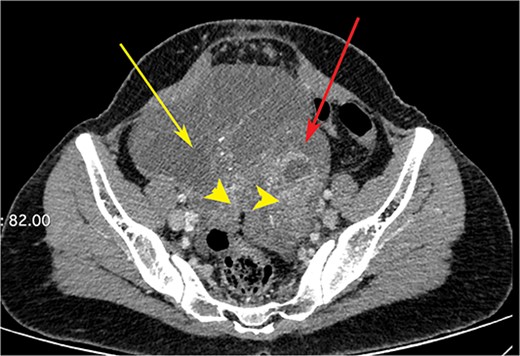

CT scan of the abdomen showing right ovarian cyst (yellow arrow), left ovarian cyst (red arrow) with solid elements within (arrow heads).